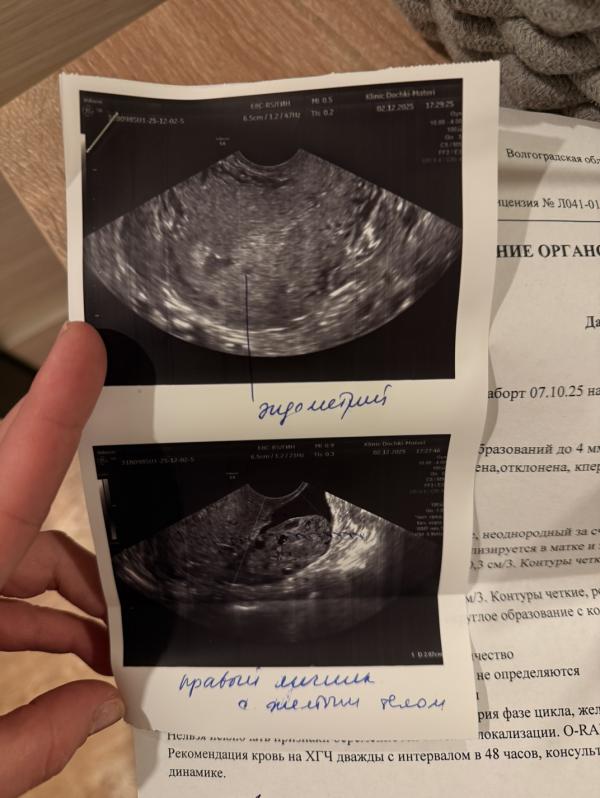

Желтое тело работает во всю, вон оно какое большое 20 мм и кровоток есть.

Эндометрий хороший пышный. Такой пышный это косвенный признак беременности.

У вас только только тесты стали полосатить. Хгч с такими полосками от силы не более 20. А плодное яйцо с хгч от 1000 только видно в матке

Эндометрий пышный очень, это косвенный признак маточной беременности

Ну тесты пока не являются положительными , как бы не хотелось. Так как нет ярких четких полосок , но призраки я тоже вижу, по УЗИ ставлю на беременность. Жёлтое тело и эндометрий шикарны )